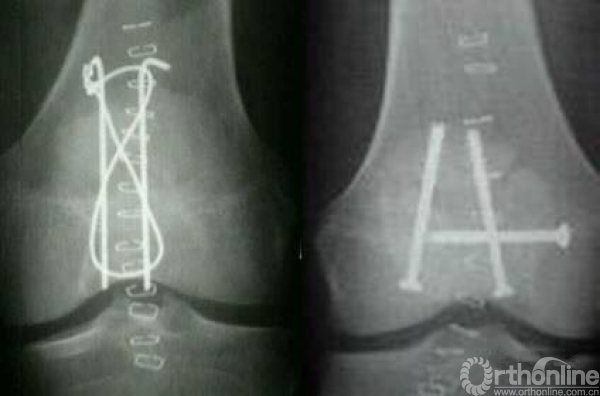

9.手术有哪些方式?张力带/拉力钉/张力带+拉力钉/部分髌骨切除/全部髌骨切除.

文献报道:骨折修复比髌骨切除更好的保留了伸膝装置,并获得了更好的功能随访,髌骨切除的病人会降低股四头肌的肌力,恢 复时间更长。